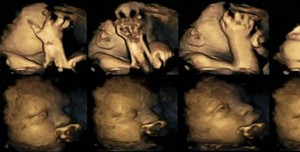

Daily Mail’de yayınlanan bir araştırmada sigara içen ve içmeyen annelerin bebeklerinin 4D ultrason görüntüleri yayınlandı.

Sigara içen annelerin bebeklerinin içmeyenlere göre daha fazla ağzına ve burnuna dokunduğu tespit edildi. Fetüsler doğum yaklaştıkça gelişime bağlı olarak yüzlerine daha az dokunuyor. Yayınlanan görüntülerde sigara içen annenin bebeğinin daha fazla yüzüne dokunduğu ve gelişmesinin engellendiğini belirtiliyor. Araştırmacılar yayınladıkları görüntülerle hamilelikte sigara içenlerin bu alışkanlıktan vazgeçeceğini umut ediyor.